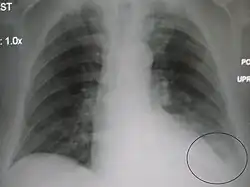

AP CXR showing left lower lobe pneumonia associated with a small left sided pleural effusion -

AP CXR showing right lower lobe pneumonia -

AP CXR showing pneumonia of the lingula of the left lung -

Right upper lobe pneumonia as marked by the circle. -

Left upper lobe pneumonia with a small pleural effusion.

Right lower lobe pneumonia as seen on a lateral CXR

The discovery of x-rays made it possible to determine the anatomic type of pneumonia without direct examination of the lungs at autopsy and led to the development of a radiological classification. Early investigators distinguished between typical lobar pneumonia and atypical (e.g. Chlamydophila) or viral pneumonia using the location, distribution, and appearance of the opacities they saw on chest x-rays. Certain x-ray findings can be used to help predict the course of illness, although it is not possible to clearly determine the microbiologic cause of a pneumonia with x-rays alone.